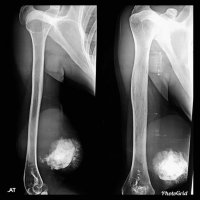

EXTRASKELETAL OSTEOSARCOMA

ESOS appears as soft tissue density with a variable amount of calcification which represents osteoid matrix formation, and is seen in -50% of cases.